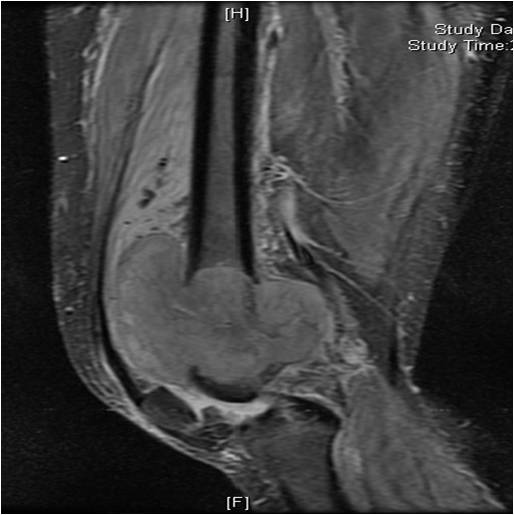

On radiographs, most MFHs of Bone are located in the metaphysis and present as purely osteolytic permeative lesions without a periosteal reaction and without mineralization (Fig. 1 &2). On MR images, MFH of Bone has ill-defined margins usually with cortical destruction of bone and extension into the soft tissues. It is usually hypo- or isointense to muscle on T1-weighted images (Fig. 3) and heterogeneous high intensity on T2-weighted images (Fig. 4-6).

Fig. 4-6: MRI Axial (Fig. 4) and (Fig. 5) T2 –weighted fat-suppressed images show a heterogeneous lesion in the distal femur. Axial T2- weighted fat suppress image (Fig. 6) demonstrates a heterogeneous lesion with hyperintense areas admixed with hypointense signal areas concordant with hemorrhage and necrosis. High grade sarcomas are commonly associated with hemorrhage and necrosis.